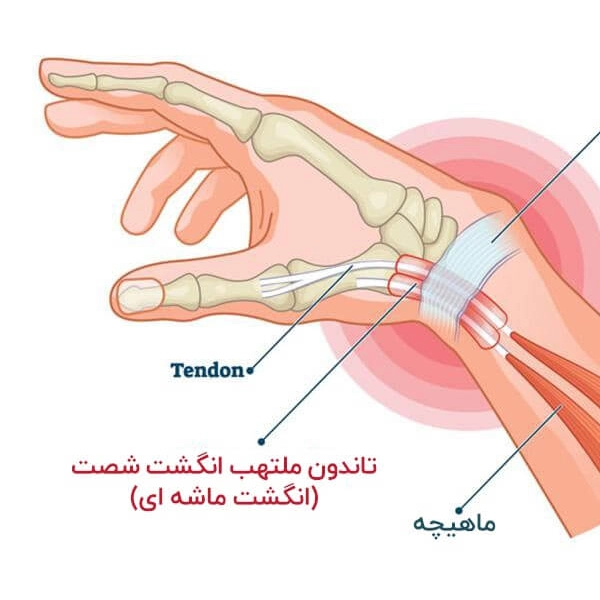

رباطهای مچ دست وظیفه اتصال استخوانهای این ناحیه را بر عهده دارند و به حفظ تعادل و پایداری مفصل کمک میکنند. پارگی رباط میتواند جزئی یا کامل باشد که در موارد شدید، بیثباتی مچ دست را به همراه دارد. این عارضه ممکن است در اثر آسیبهای ورزشی، زمین خوردن روی دست یا حتی حرکات تکراری مچ دست رخ دهد. شدت آسیب تعیینکننده تعداد جلسات لازم برای درمان و بهبودی کامل خواهد بود.

- پیوند تاندون (در پارگیهای شدید):

اگر رباط آسیبدیده بیش از حد ضعیف شده باشد، از بافت تاندون دیگر بدن (مانند تاندون ساعد) برای جایگزینی استفاده میشود. این روش معمولا نیازمند دوره نقاهت طولانیتر است.